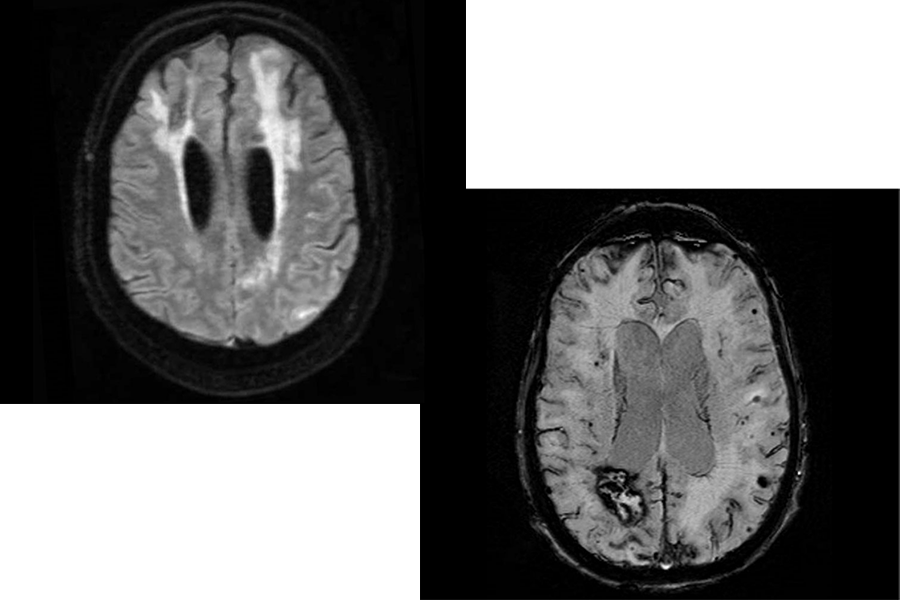

Left: Image from a fluid-attenuated inversion recovery (FLAIR) sequence from an MRI showing the imaging signature of CAA-ri: asymmetric cortical and subcortical hyperintensities suggestive of vasogenic edema and sulcal effusion. Right: Susceptibility-weighted imaging sequence of an MRI showing multiple imaging hallmarks of CAA: lobar intracerebral hemorrhage, multiple lobar microhemorrhages, and cortical superficial siderosis.